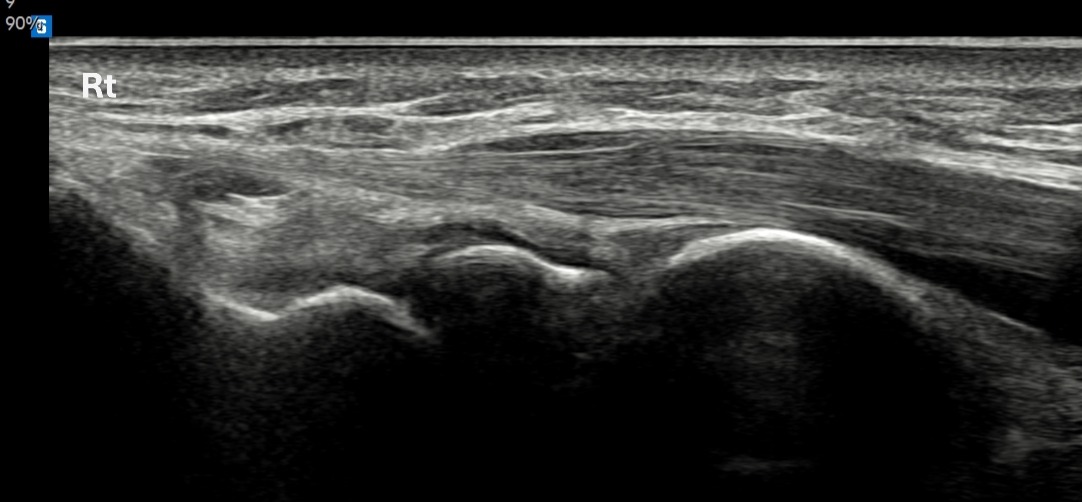

치료 후기에 사용된 전/후 검사 사진은 동일 인물의 결과이며 각 지점 동일 조건에서 촬영되었습니다.

개인에 따라 치료 결과에 차이가 있을 수 있으며, 부작용이 발생할 수 있습니다. 내원 후 충분한 상담을 받으시고 치료를 진행하시면 됩니다.

- 치료기간 : 25 . 5 . 13 ~ 25 . 6 25.

- 치료횟수 : 10 회, 한약 1개월 + 라이넥 10회 + 극초단파 10회